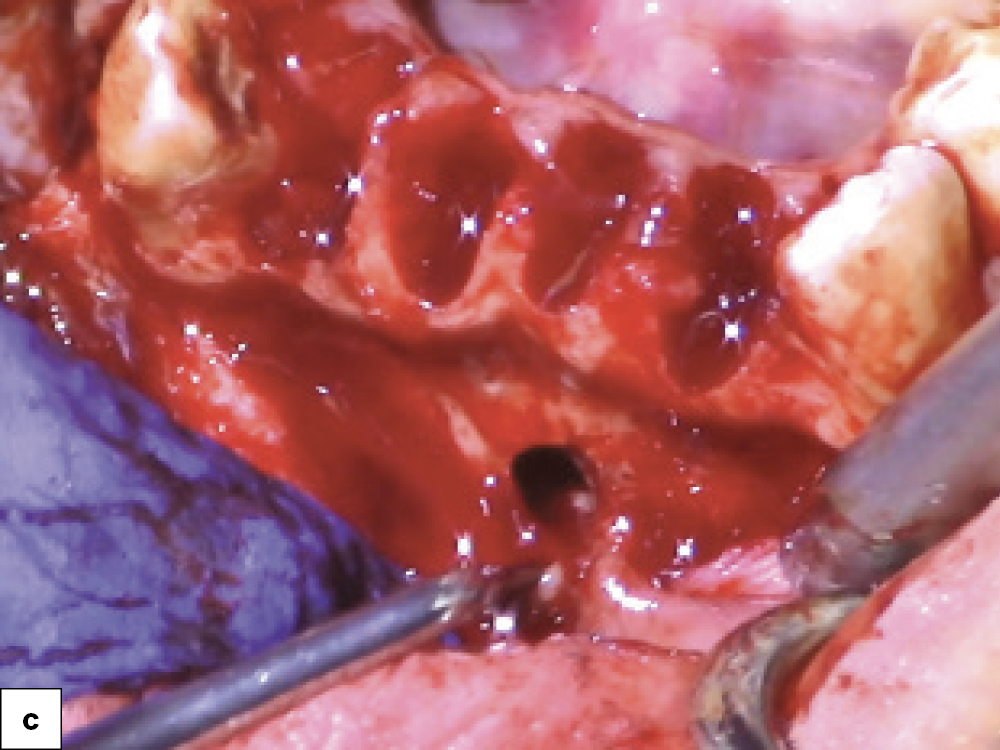

Bony Defect Evaluation A

Bony Defect Evaluation B

Bony Defect Evaluation C

Bony defect evaluation: (a) Flap reflection allows the clinician to visually evaluate the size and location of the fenestration to determine whether the defect will compromise implant positioning or primary stability when immediate implant placement is desired; (b) Examples of a large fenestration (green arrow) and loss of the buccal plate (blue arrow), either of which would contraindicate immediate implant placement due to the inability to obtain primary stability; (c) Additional example of flap reflection to show the fenestration.